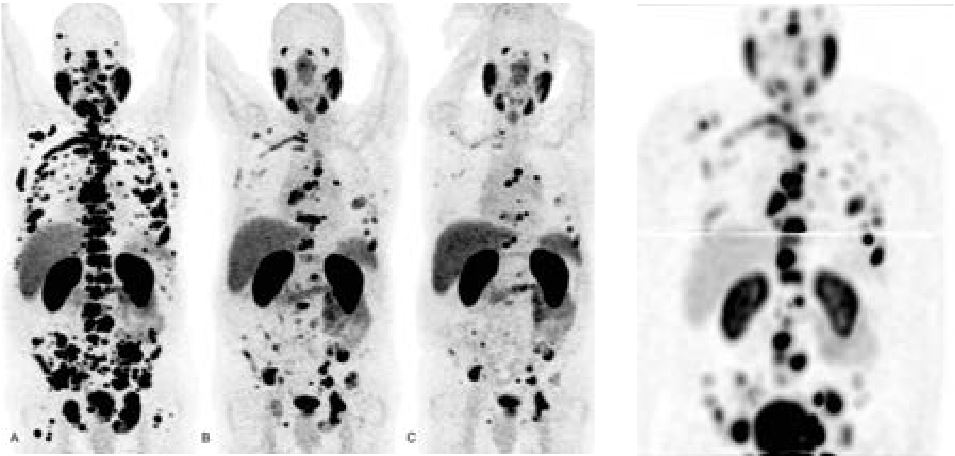

• Oncologie (métastases, tumeurs primitives, réponse au traitement...)